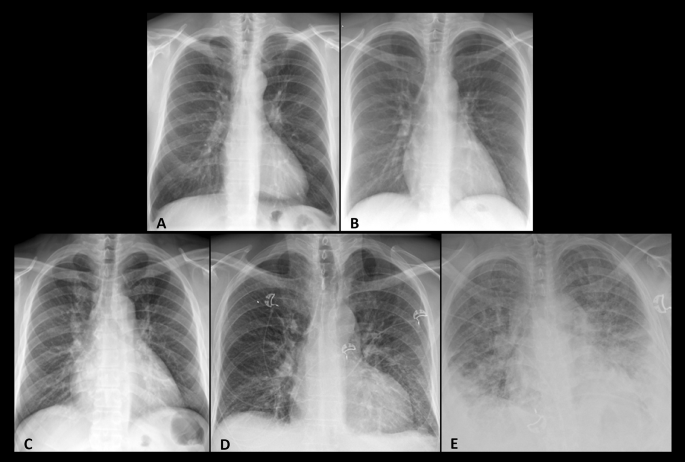

Frontal Chest X-Ray images from 5 Study Population subjects represent the pulmonary vasculature patterns of Normal physiology and increasing Pulmonary Venous Hypertension [PVH]. They include [Table 11]: Normal: Mid-to-lower lung vascular predominance (A). PVH Stage 1: Vascular redistribution (aka “cephalization”) to upper lungs without pulmonary edema. (B)PVH Stage 2-Early: Vascular redistribution/congestion with mild edema (perihilar peribronchial cuffing/haziness) (C). PVH Stage 2-Late: Central vascular congestion with moderate edema (perihilar haziness plus peripheral interlobular septal thickening (i.e., Kerley B Lines)) (D). PVH Stage 3: Central vascular congestion with severe edema (perihilar and lower-lung alveolar opacification (aka “batwing” pattern)) (E).